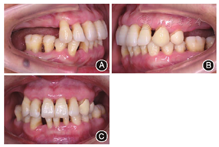

术后(3)正畸:2012年7月至2013年11月,上下颌牙齿分别开始正畸加力(图6,图7),期间每3个月进行一次牙周维护。

像;B:左侧

像;C:正面

像

像(4)种植:2013年11月,牙周复查显示牙周状况稳定,开始行